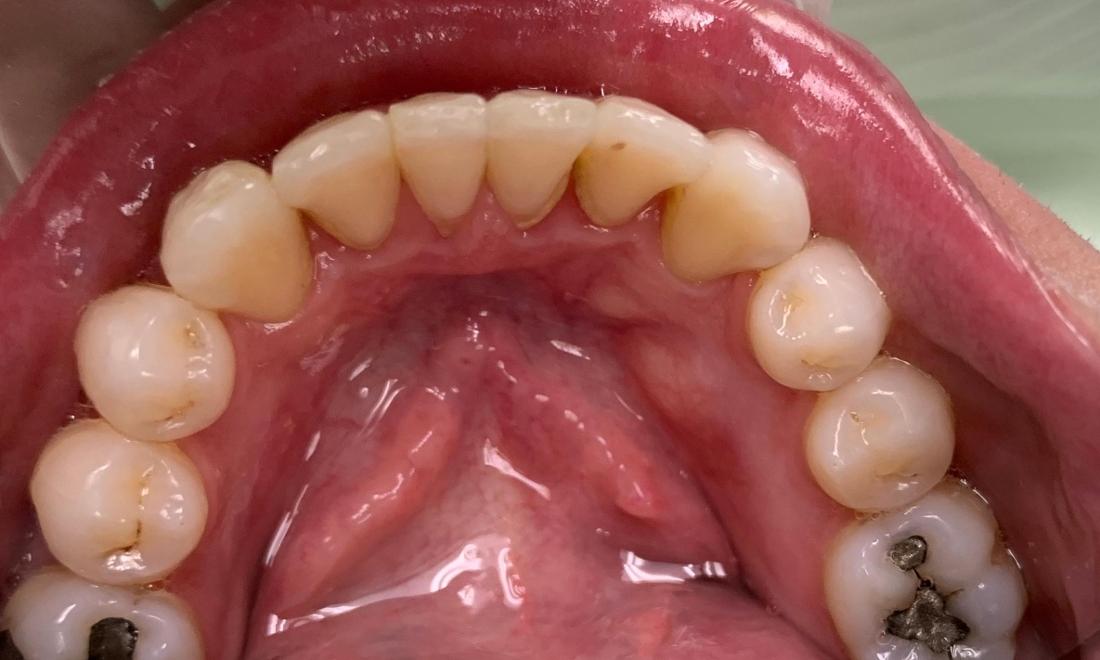

This patient's "before" photo shows their crooked, misaligned teeth and the gaps between the top and bottom rows of their smile. However, by using adult braces, we pulled their teeth into alignment and produced a straighter, healthier smile.

Clear braces allow you to achieve a straighter smile while still maintaining a sleek, professional appearance. Invisalign can help you close gaps in your smile and move teeth into proper alignment, making them easier to clean and keep cavity-free.